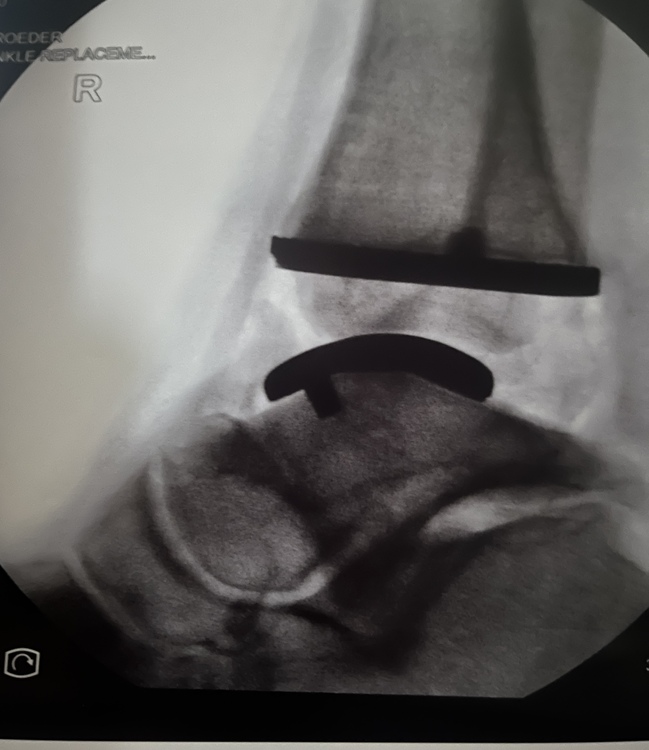

I had my total ankle replacement surgery this morning and I’m back home recovering. I thought I’d share for those interested. Pre op and current view of my right ankle. The climbing shoes provide a reference point for my pre op ankle. |

TK421wrote: Which TAR do you have yourself? Do you have any images to share or you TAR? |